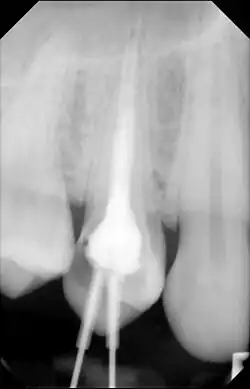

Diagnosis typically involves a clinical examination by a dentist or endodontist, complemented by imaging studies such as cone-beam computed tomography. Radiographically, condensing osteitis presents as a localized radiopaque lesion at the root apex of the affected tooth.[5]